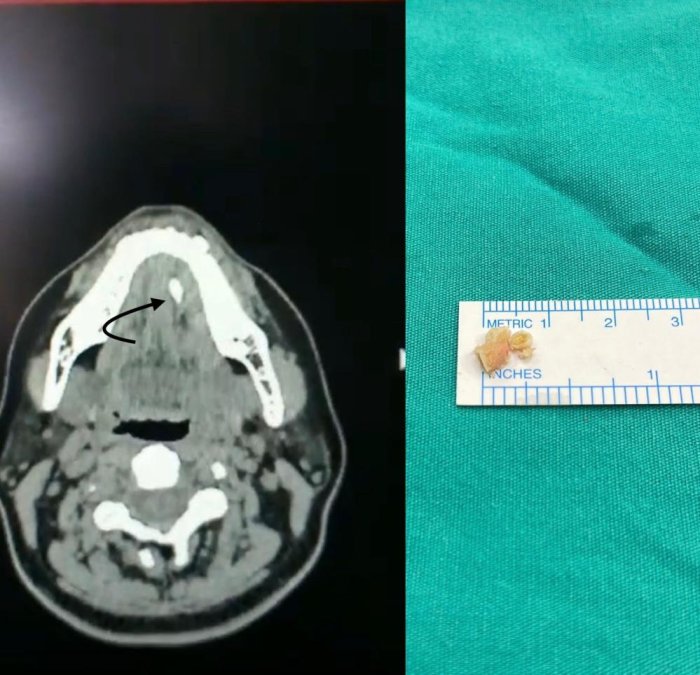

Şikâyetleri daha hafif olan ve taş boyutları küçük ve tükürük bezi kanalının ucuna yakın yerde yerleşim gösteren hastalarda geleneksel tedaviler önerildiğini dile getiren Doç. Dr. Nesrettin Fatih Turgut, “Ağrı kesiciler fayda sağlar. Bol sıvı tüketimi, ısı uygulaması rahatlama sağlayabilir, bol sıvı tüketimini tüm hastalarımızda önermekteyiz. Aynı zamanda limon gibi ekşi ürünlerin emilmesi tükürük sıvısını artırır ve çok küçük taşların dışarı atılmasını sağlayabilir. Taş boyutunun büyük olması, taşında daha çok beze yakın yerde yerleşmiş olması durumlarında ise cerrahi uygulamaları gündeme gelmektedir. Taş yerleşimi, büyüklüğü etkilenen tükürük bezinin durumu cerrahinin şeklini belirler. Eğer taş tükürük bezi kanalında yer alıyorsa, sialendoskopi olarak adlandırılan kamera sistemi ile yer tespiti ve çıkarma işlemi herhangi bir kesi olmaksızın tercih edilir. Ancak taşın tükürük bezi içerisinde yer alması, boyutunun çok büyük olması durumlarında ise dışardan veya ağız içinden yaklaşım ile cerrahi seçenekleri gündeme gelmektedir” diye konuştu.

“Büyük taşlar havalı kırma tekniği kullanılarak küçültülerek çıkarılıyor”

Tükürük bezi kanallarının içindeki en uç bölgelere kadar ulaşabilen bir kamera sistemini kullanarak tükürük kanallarını inceleme yöntemi olan sialendoskopiden bahseden Doç. Dr. Turgut, “Bu sistem, kanal içindeki hastalıkların tanısı ve tedavisi için bir araç sağlar. Kamera sisteminin temel özelliği, tükürük kanalının içini milimetrik boyutlarda kontrol etme yeteneğidir, yaklaşık 1.5 mm'lik bir boyuttan bahsedilmektedir. Bu işlem genel anestezi veya lokal anestezi altında uygulanabilir. Hekimin deneyimi, hastanın sağlık durumu, hastanın uyumuna ve tercihine bağlı olarak tedavi planlaması yapılır. Sialendoskopi, genellikle tükürük kanallarında taş olan hastaların tedavisinde kullanılmaktadır. Ayrıca Sjögren hastalığı, radyoaktif iyot tedavisi almış hastalar ve tekrarlayan tükürük bezi iltihaplarına sahip çocuk hastalarda da bu yöntem uygulanabilir. Sialendoskopi süresi, taşın büyüklüğü ve konumuna bağlı olarak değişebilir. Büyük taşlar havalı kırma tekniği kullanılarak küçültülerek çıkarılır, bu nedenle işlem süresi uzun olabilir. Sialendoskopi sırasında herhangi bir kesi veya dikiş uygulanmaz, bu nedenle işlem sonrasında ağrı veya şikâyet gözlemlenmez. Geçici olarak aynı taraftaki tükürük bezinde şişlik olabilir ancak genellikle bu şişlik 1-2 saat içinde azalır. Hastalar, genellikle aynı gün içinde taburcu edilirler” şeklinde konuştu.

“Sialendoskopi ile çıkarılamayan taşlar için açık cerrahi uygulanabilir”

Cerrahi müdahale seçeneği hakkında da bilgi veren Turgut, “Taş boyutunun büyük olması, taşın bez içinde yerleşim göstermesi, sık enfeksiyona bağlı taşın kanala yapışık olması gibi nedenlerden dolayı sialendoskopi ile taşın çıkarılması mümkün olmayabilir. Bu durumlarda açık cerrahi seçeneği gündeme gelir. Eğer taş, kanal içinde yerleşim gösteriyorsa ağız içerisinden kanal üzerinde yapılacak ufak bir kesi ile taşa ulaşılır ve taş çıkarılır. Birkaç dikiş atılarak işlem tamamlanır. Hastalarımız ancak taş tükürük bezi içinde olursa veya tükürük bezi sürekli (kronik) enfeksiyona bağlı olarak işlevini yitirmişse (atrofiye uğramış) tükürük bezi genel anestezi altında çene altından kesi yapılarak tamamen çıkarılır. Ameliyat sonrası 2-3 gün hastane yatışı gerekebilir” ifadelerini kullandı.